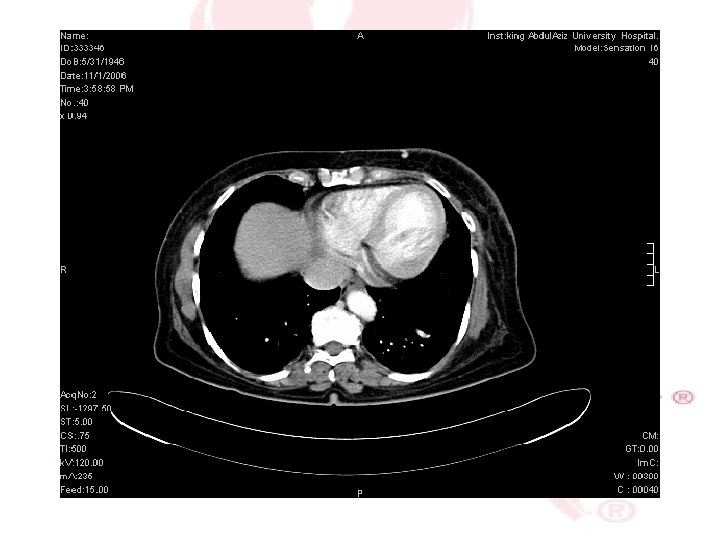

CT SCAN CHEST , ABDOMEN &PELVIS